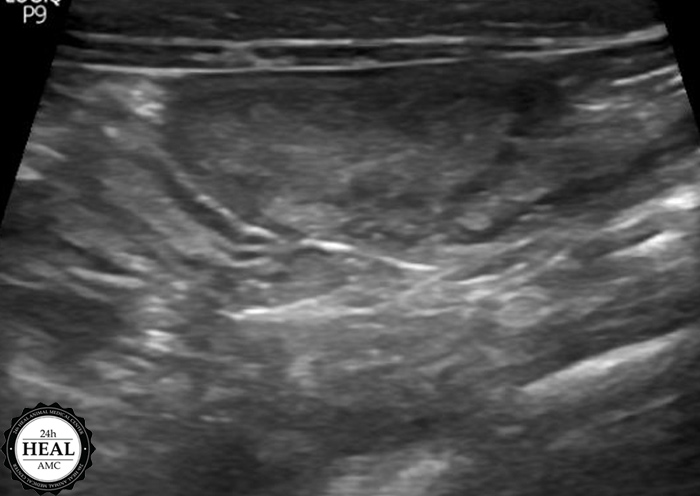

정확한 원인을 파악하기 위해 방사선, 초음파 검사를 실시했습니다.

초음파 검사 결과 미*는 자궁 내 농성이물이 의심되는 소견이 있었습니다.

추가적으로는 구토, 설사, 체중 감소, 복압 항진 등이 있습니다.고양이 자궁축농증 진단 초음파를 통해 가장 정확한 진단이 가능하며, 추가적으로는 혈액검사, 소변검사 등이 필요하였습니다.